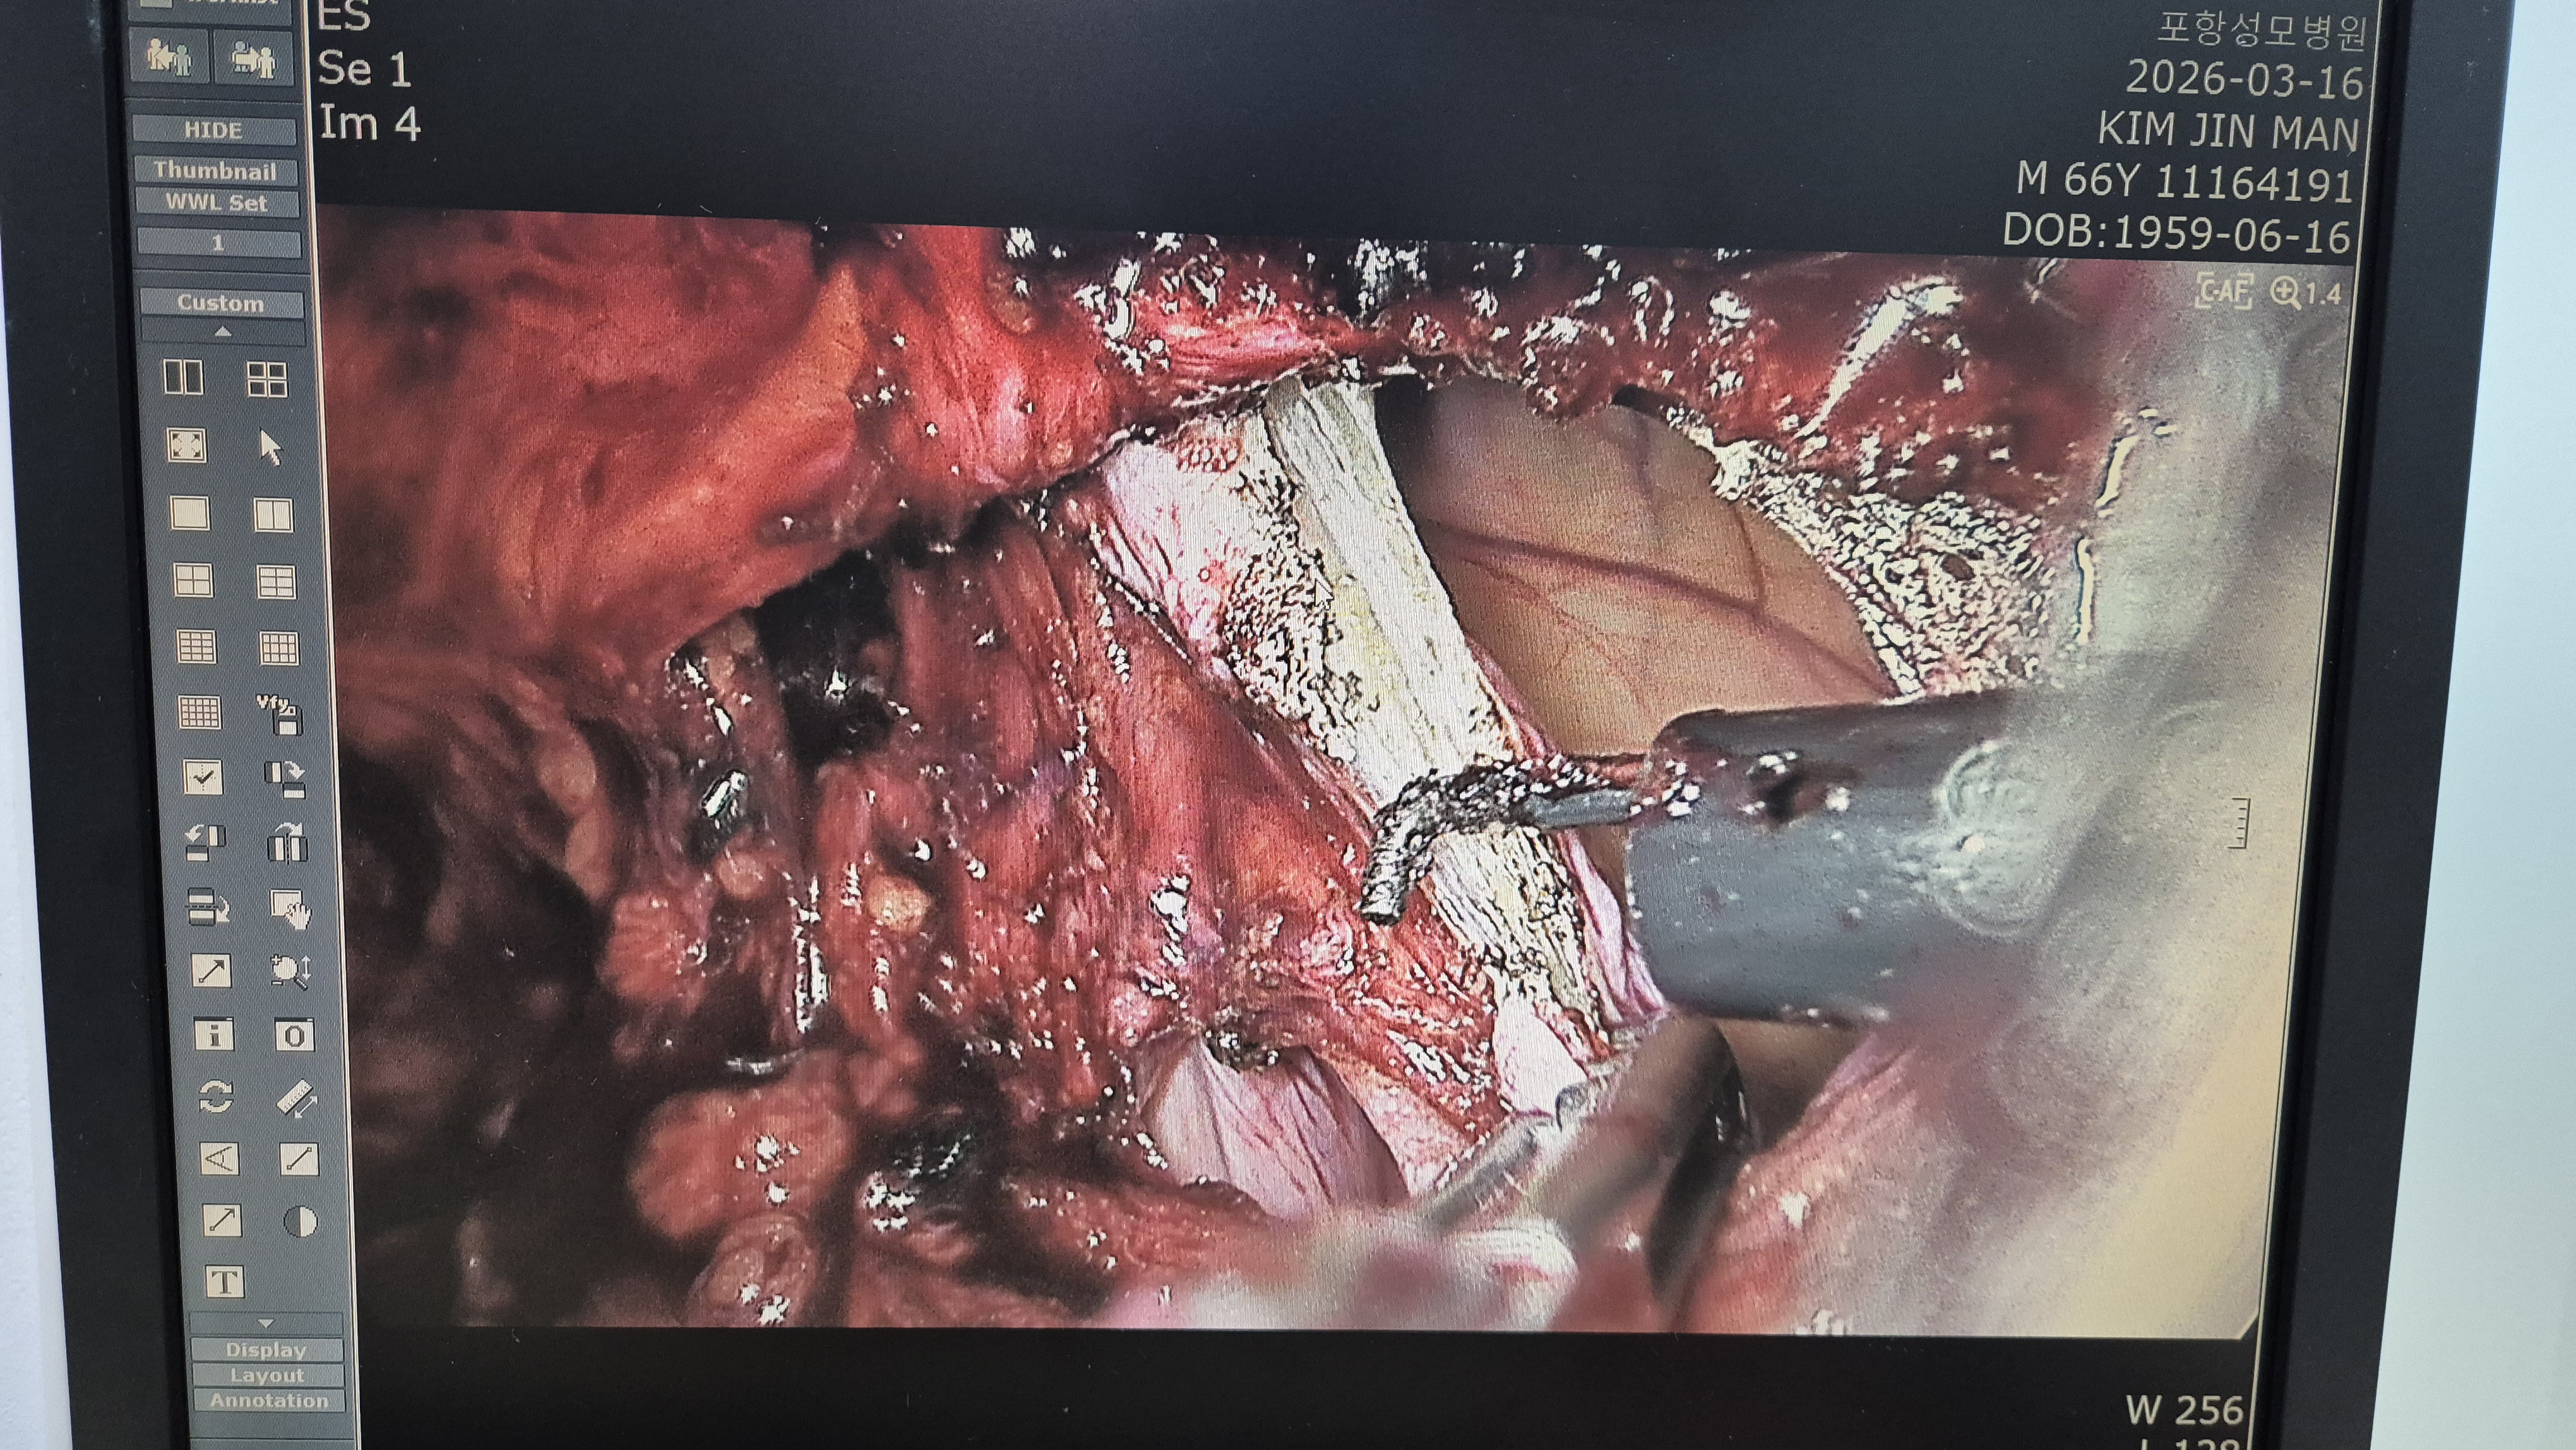

1개월전 우측 탈장 수술 하신분으로

우측 서혜부 종물로 다시 내원하여 서혜부 탈장 재발로 확인되어,

복강경 탈장교정술을 시행했습니다.

기존 mesh가 위로 이동하면서 재발 발생.

복막박리.

메쉬로 고정.

수술은 35분 걸렸습니다.